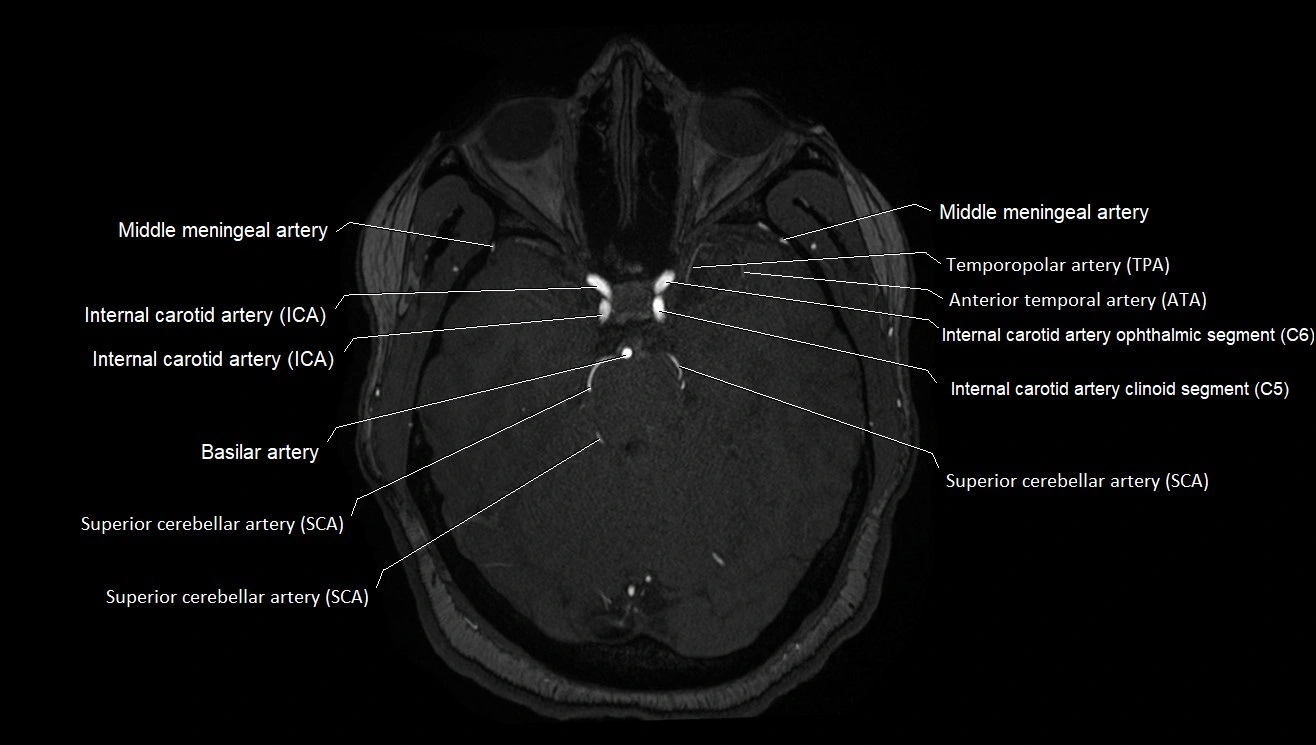

MRI images

image